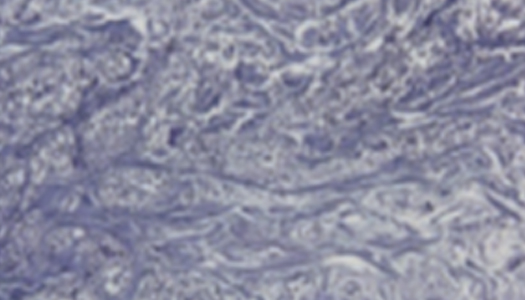

• 콜라겐

3MONTH

• 엘라비에 리투오

6MONTH

• 엘라비에 리투오2.9배 증가

• 엘라비에 리투오3.2배 증가

리투오가 비교 대조군 대비 콜라겐 생성효과가 뛰어남을 확인

*파란색이 콜라겐